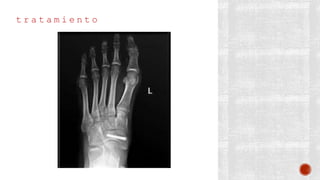

t r a t a m i e n t o

¬ Conservador: Yeso corto durante 2 a

4 semanas

¬ Quirúrgico:

- Primero y quinto metatarsianos:

Reducción abierta y fijación interna

crucial